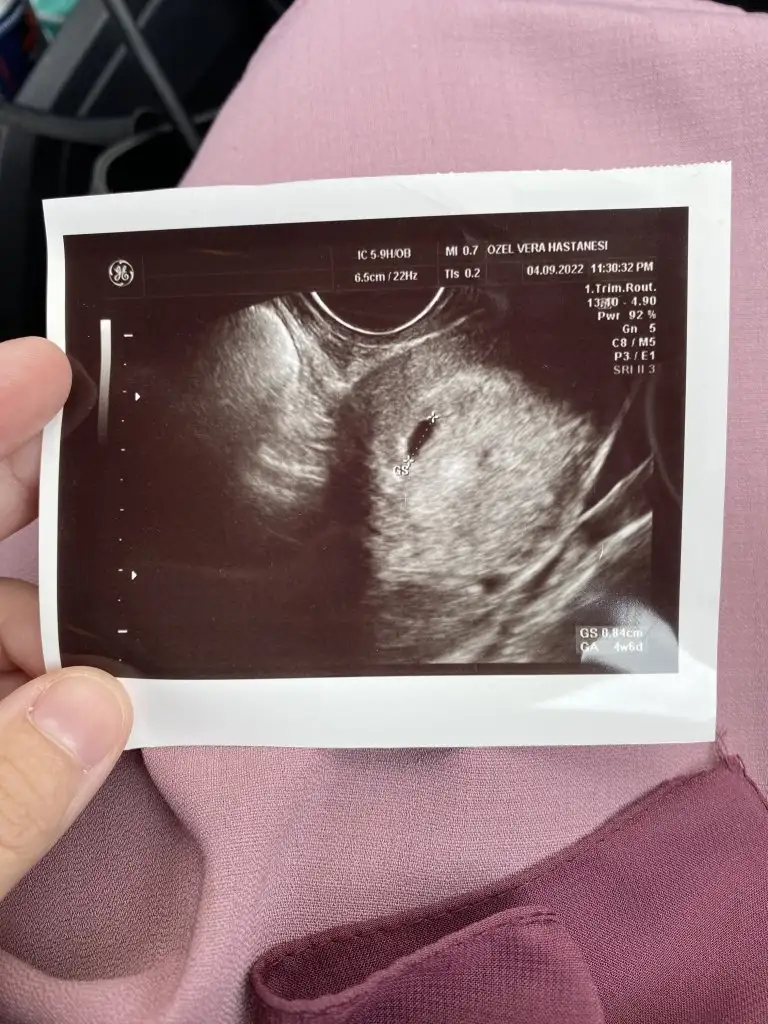

Merhaba arkadaslar hatirlarsaniz betam adetten 3 gun once 12,5 du sukur artisim'guzel devam etti suan keseyi gorduk normalde 5+3 ken adete gore ultrasonda 4+6 dedi normal gelisimi dedi haftaya insallah tekrar cagirdi o zaman bebegi de goruruz dedi 2 ci fotoda ekrandan cekmistim yolk kesesi az gozukuyor bebekde bunun uzerinde haftaya net belli olur dedi insallah bana dua edin hersey yolunda gitsin bu defa insallah henuz kimseye demiyorum yine husran olursa diye hemde nazar dan korkuyorum

Eklentiler

• C0025D05-60E2-421E-80B3-C99EEDC002E7.webp

79,5 KB · Görüntüleme: 85